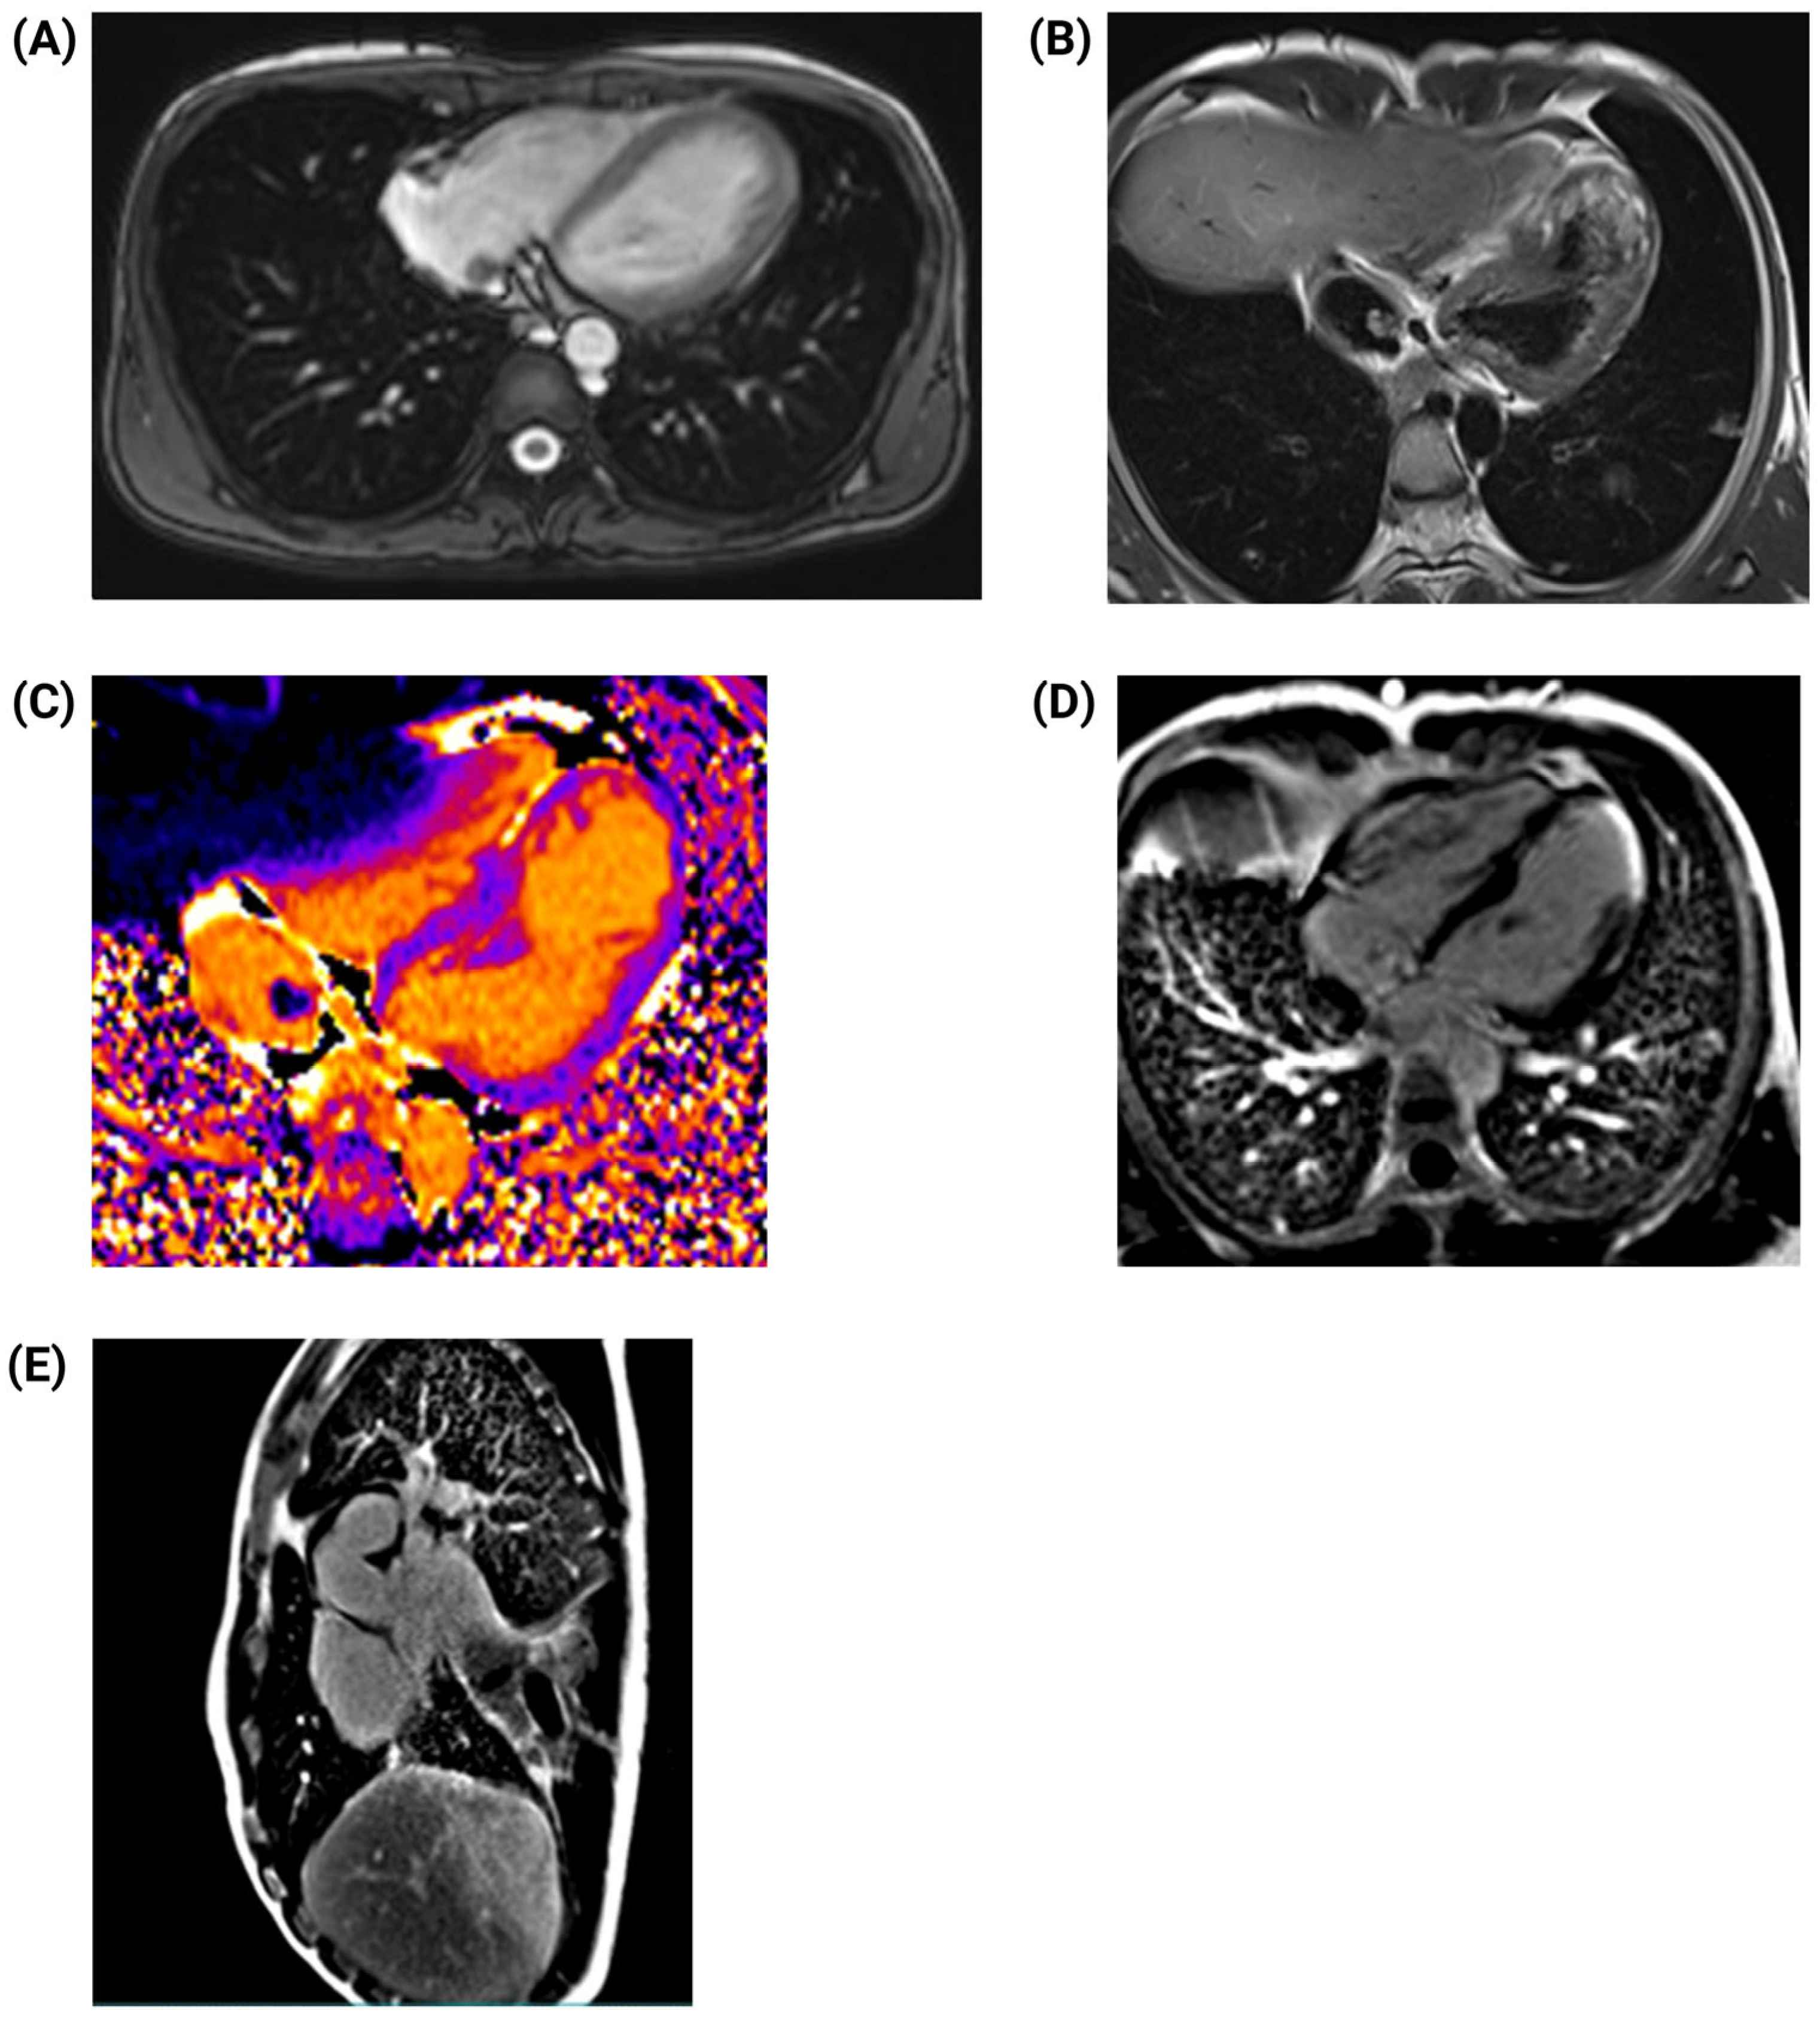

2. Case Presentation